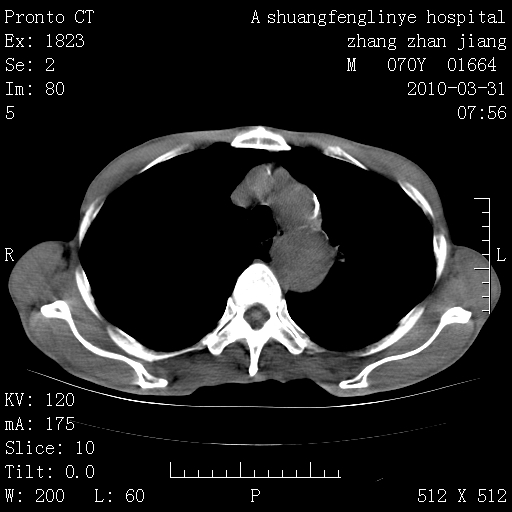

双上肺继发型tb并左上空洞形成,主动脉冠脉钙化。

支持:继发性肺结核伴空洞形成!建议纤支镜检查待出外周围型肺癌可能!

1)两肺上叶继发性肺结核并左肺上叶空洞形成。2)冠状动脉及主动脉钙化。